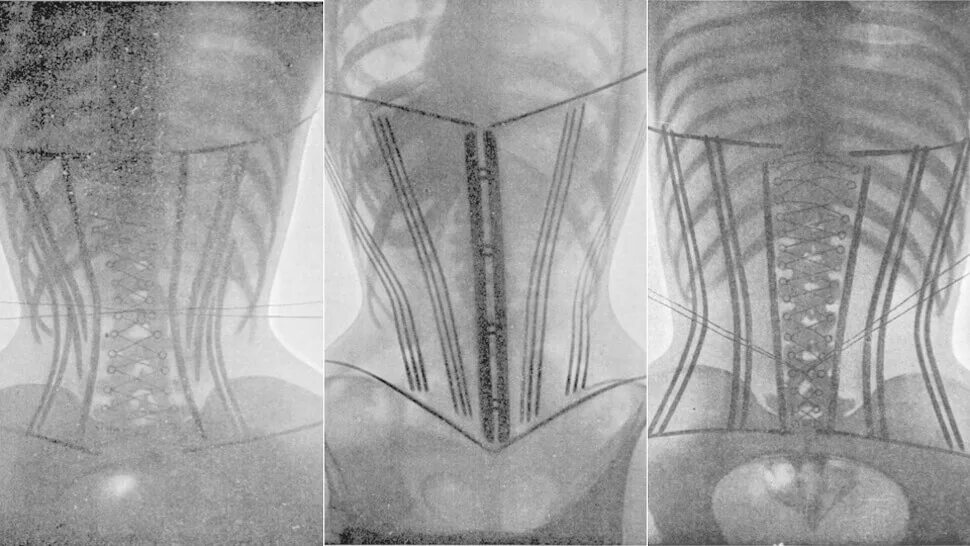

Последствия ношения корсета. смещение органов в корсете. деформация ребер от корсета. корсет деформация внутренних органов.Корсеты 18 века деформация органов. корсет деформация внутренних органов. деформация ребер от корсета. смещение органов из-за корсета.Последствия ношения корсета. органы от корсета. деформация органов от корсета. смещение органов в корсете.Корсеты 18 века деформация органов. корсет 19 века деформация ребер. корсет деформация внутренних органов. рентген женщины в корсете.Корсеты деформация органов. деформация внутренних органов от корсета.Влияние корсета на внутренние органы. последствия ношения корсета. человеческий организм с корсетом. внутренние органы после корсета.Корсеты деформация органов. искривление ребер от корсета. деформация внутренних органов от корсета.Деформация органов от корсета. корсет и внутренние органы. внутренние органы после корсета.Последствия ношения корсета. смещение органов в корсете. деформация ребер от корсета.Внутренние органы после корсета. корсет деформация внутренних органов. влияние корсета на внутренние органы. деформация внутренних органов из-за корсета.Последствия ношения корсета. деформация органов от корсета. корсеты 18 века последствия.Корсет 19 века викторианская эпоха. корсет 19 век. корсет екатерины медичи. корсеты 19 века последствия.Корсет 19 века деформация ребер. корсеты 18 века деформация органов. корсет карикатура.Корсет внутренние органыКорсеты 18 века последствия. деформация скелета от корсета. последствия ношения корсета. деформация ребер от корсета.Корсет шено. сколиоз корсет шено. корсет шино. корсет шено для позвоночника.Корсет внутренние органыИспанский корсет 16 века. корсет екатерины медичи. корсаж испания 16 век. металлический корсет.Корсет титаник. корсет женский. платье с корсетом. корсеты женские утягивающие под одежду.Платье с корсетом. корсет женский. металлический корсет. корсет удлиненный.Моделирование корсета. основа для корсета. лекала для пошива корсета. техника пошива корсета.Корсет massimo monteforte. кожаный корсет. корсет из кожи. корсет маленький.Органы человека. внутренние органы человека. внутреннее строение человека. внутренние органы человека по отдельности.Тривес эволюшн бандаж корсет. корсет trives evolution t1591. корсет ортопедический т-1503. 58.93 корсет ортопедический.Корсетная школа ирины павшиной. изнанка корсета. пошив корсета прозрачного.Шьем корсет. платье с корсетом. изнанка корсета. корсетная застежка.Шитье корсета. корсеты технология пошива. платье с корсетом пошив. корсет для шитья платья.Корсет на пояснично-крестцовый отдел позвоночника 011b. корсет для грыжи л5 с1. корсет ortex 011c. корсет orlett ibs-2004.Корсет тривес т-1503. корсет trives evolution t1591. корсет ортопедический т-1503 черный “тривес evolution”. 58.93 корсет ортопедический.Корсет внутренние органыДетали корсета. детали корсета названия. корсет по мюллеру. техническое описание корсета.Анатомия органов грудной клетки. внутренние органы человека с ребрами.Корсет massimo monteforte. пояс uterque корсет. короткий прозрачный корсет. платье с корсетом.Анатомия человека внутренние органы. анатомия женских органов. внутреннее строение человека внутренние органы.Корсет внутренние органыШитье корсета. шьем корсет. моделирование корсета. лекало корсета.Корсет внутренние органыСтроение тела женщины. внутренние органы женщины. анатомия человека внутренние органы. организм женщины.Мышечный корсет спины. мышечный корсет живота. мышцы антагонисты живота.Анатомия человека внутренние органы. внутренние органы рисунок. анатомические рисунки органов. анатомический рисунок человека внутренние органы.Корсет внутренние органыКорсет внутренние органыКорсет с чашечками. корсет с чашками. корсет прозрачный с чашками. корсет с отрезной чашкой.Корсет внутренние органыПошив корсета с чашечками. пошив корсета мастер класс. корсет мк. корсеты технология пошива.Real doctors корректор осанки. леомакс корректор осанки. корректор осанки для женщин леомакс. магнитный корсет.Корсет ottobock lumbo direxa 50r50. orlett ibs-2004. корсет ottobock dorso direxa posture 50r59. корсет heb 997 28 r16.Внутренние органы человека со спины.Корсет эббота-шено. корсет функционально-корригирующий шено. корсет шено для позвоночника кифоз. шино корсет корсет шено.Платье с корсетом. корсет с чашками. шитье корсета. моделирование корсета.Схема внутренних органов. органы брюшной полости. внутренние органы вид сбоку.Корсет внутренние органыШнуровка корсета схема. схема завязывания корсета. как шнуровать корсет схема. как правильно завязать корсет.Корсет внутренние органыКорсет для куклы барби выкройка. лекало корсета. выкройка корсета. выкройка корсетного платья.Корсет 2025 референс. моделирование корсета. платье с корсетом. корсет тканевый.Анатомия органов. анатомия человека внутренние органы. топография внутренних органов человека.Корсет внутренние органыКорсет внутренние органыОрганы человека. органы внутри человека. человек изнутри анатомия.Корректор осанки oppo medical 2175. корсет oppo medical 2263 (s). корсет oppo medical 2065 (s). корсет oppo 2261-6 (s).Корсет с чашками. корсет прозрачный с чашками. корсет полупрозрачный. корсет сетка.Внутренние органы. органы человека. макет внутренних органов человека.Корсет внутренние органыКорсет внутренние органыВнутренние органы. строение человеческих органов. человеческие органы по отдельности. внутренние органы человека в полный рост.Корсет внутренние органыКорсет внутренние органыПошив корсета с чашечками. корсеты технология пошива. корсет с чашечками платье. платье с корсетом.Женский скелет с внутренними органами. анатомия человека в полный рост внутренние органы. макет человека с органами в полный рост. строение тела женщины для детей.Корсет внутренние органыШитье корсета. корсеты технология пошива. пошив корсета с чашечками. изнанка корсета.Внутренние органы обнимаются. шуточная анатомия человека. внутренние органы обнимаются картинка. милые органы.Шьем корсет. платье с корсетом. платье с корсетом пошив. моделирование корсета.Корсет ортопедический тривес т-1560. ортопедический корсет пояснично-крестцовый т.58.10 (т-1560). тривес корсет ортопедический пояснично-крестцовый т 58.10. корсет тривес пояснично-крестцовый т 1586.Внутренние органы грудной клетки. анатомия органов грудной клетки. схема грудной клетки человека с органами. фронтальный срез грудной клетки.Футболка внутренние органы. майка с внутренними органами. футболка с принтом внутренних органов. футболка с рисунком внутренних органов.Мышечный корсет. мышечный корсет позвоночника. мышечный. мышцы спины мышечный корсет.Внутренние органы человека. анатомия человека внутренние органы. изображение внутренних органов человека.